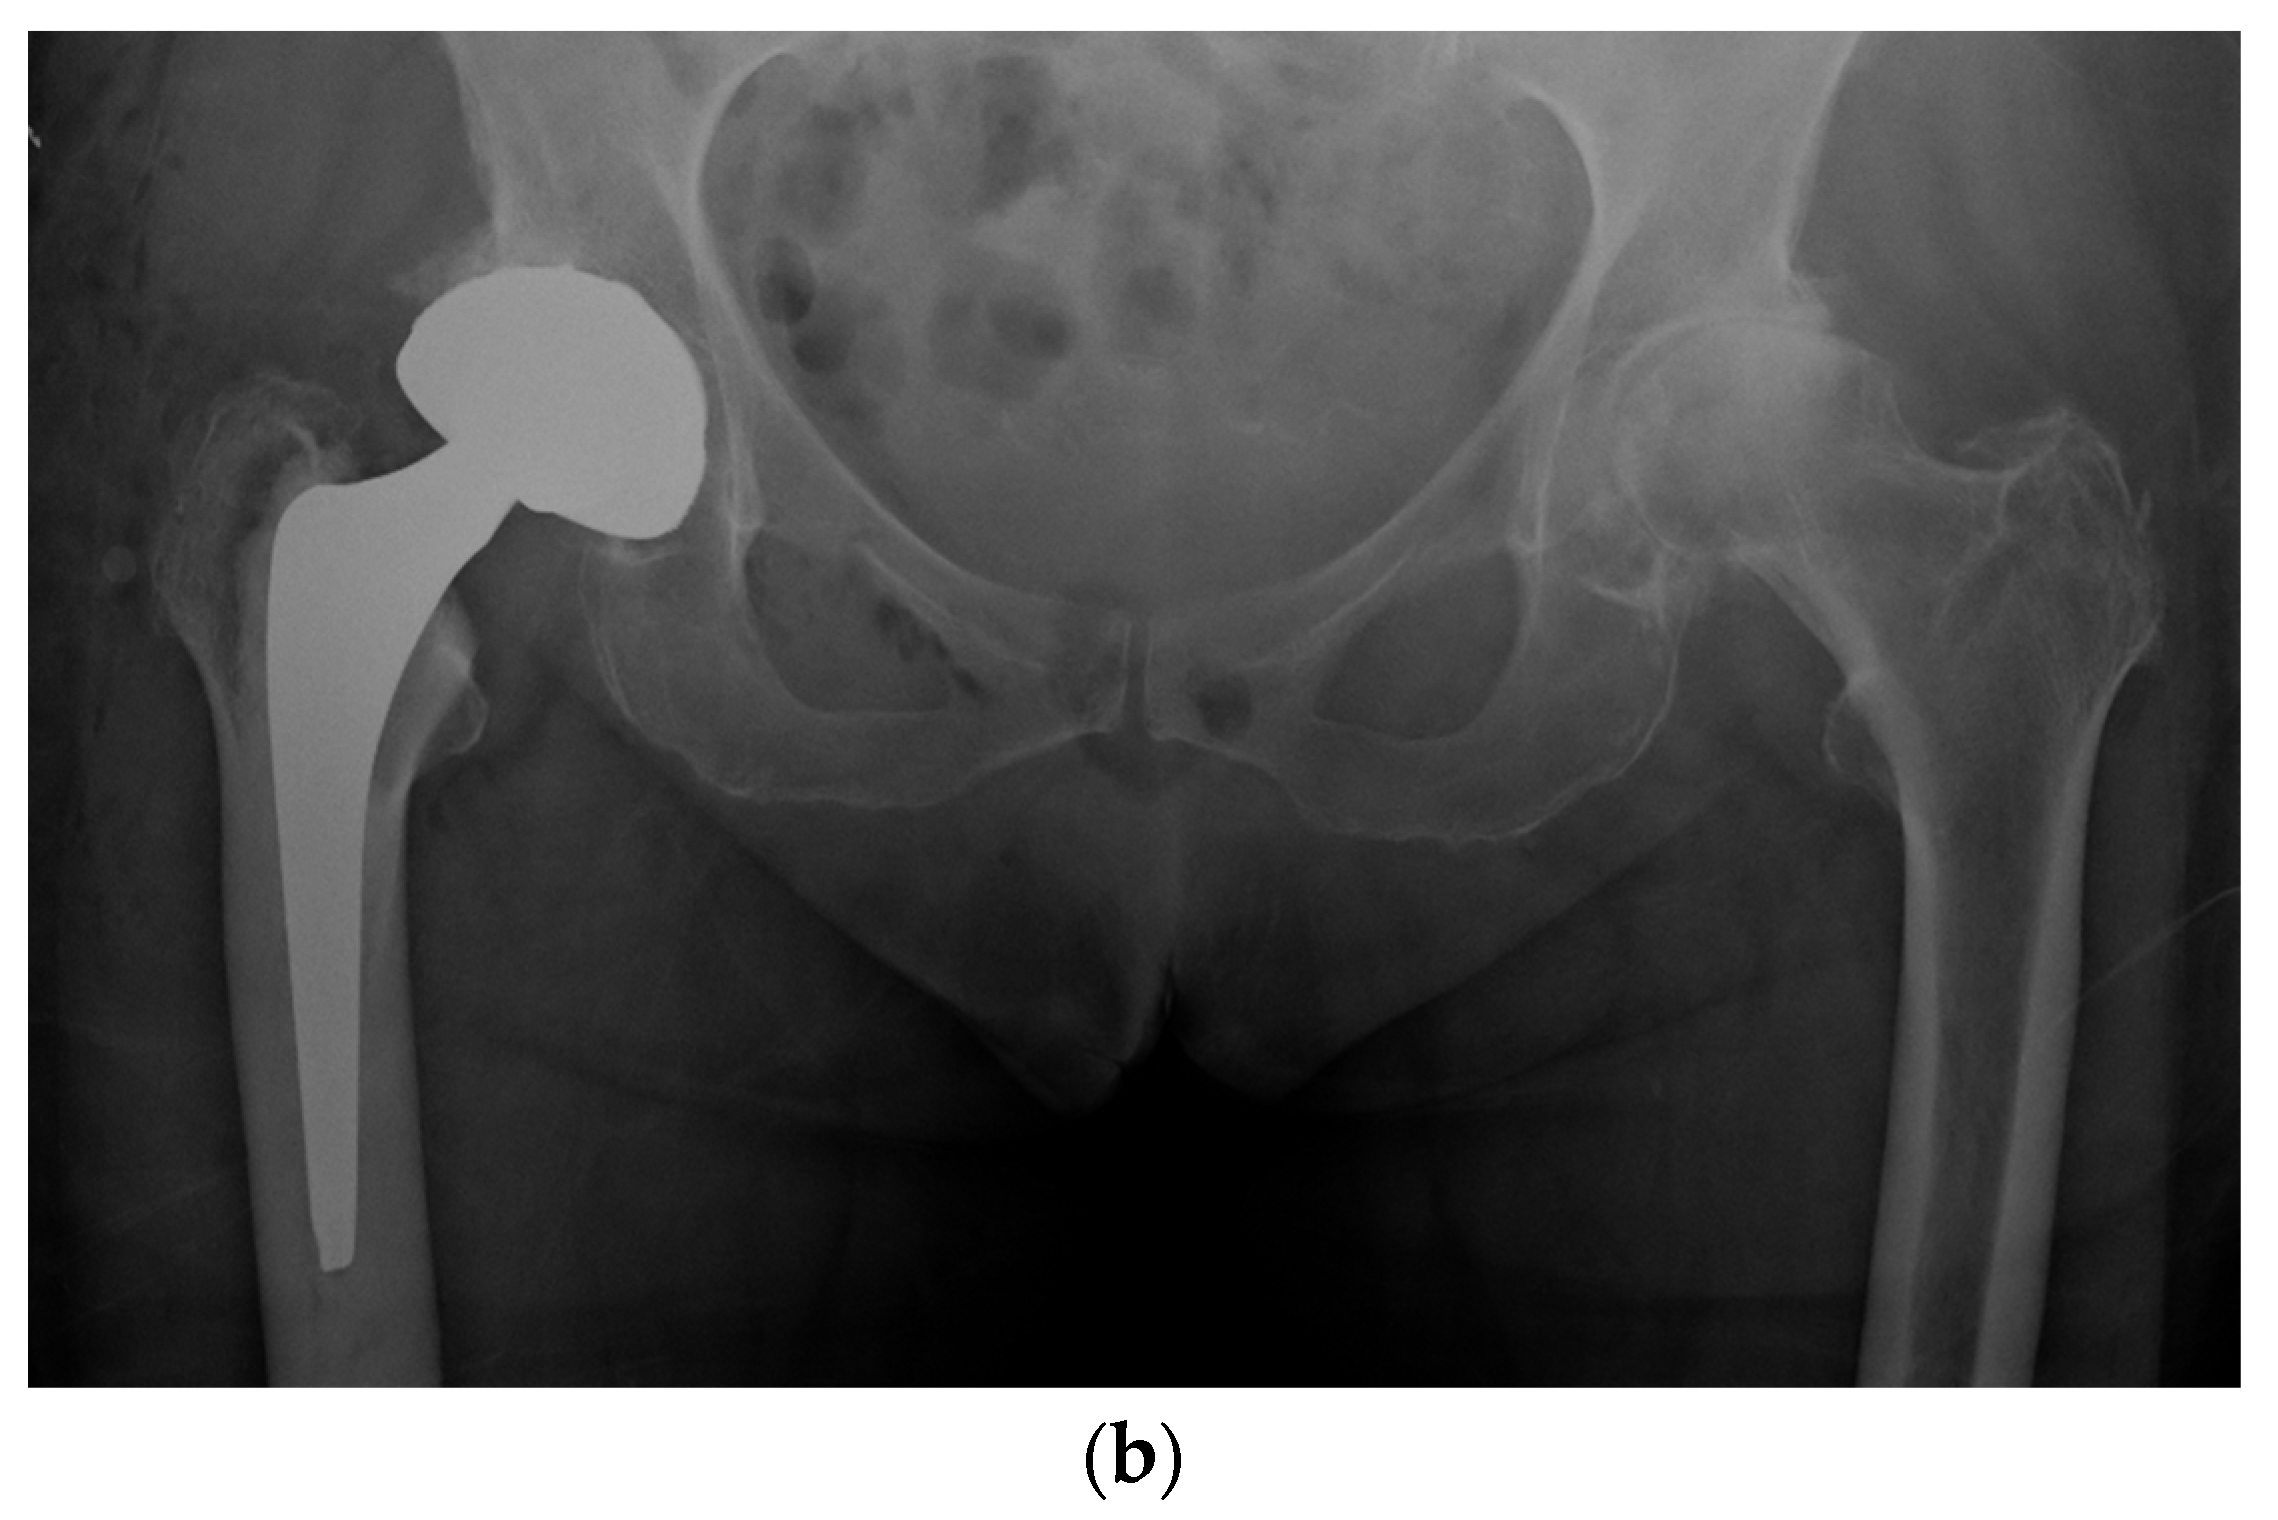

Figure 5.

(a) Antero-posterior pelvis radiograph of a 55-year-old man with a right metal-on-metal 28 mm THA and severe osteoarthritis of the left hip. (b) Postoperative radiograph after a left LDH THA with leg length and femoral offset restoration.